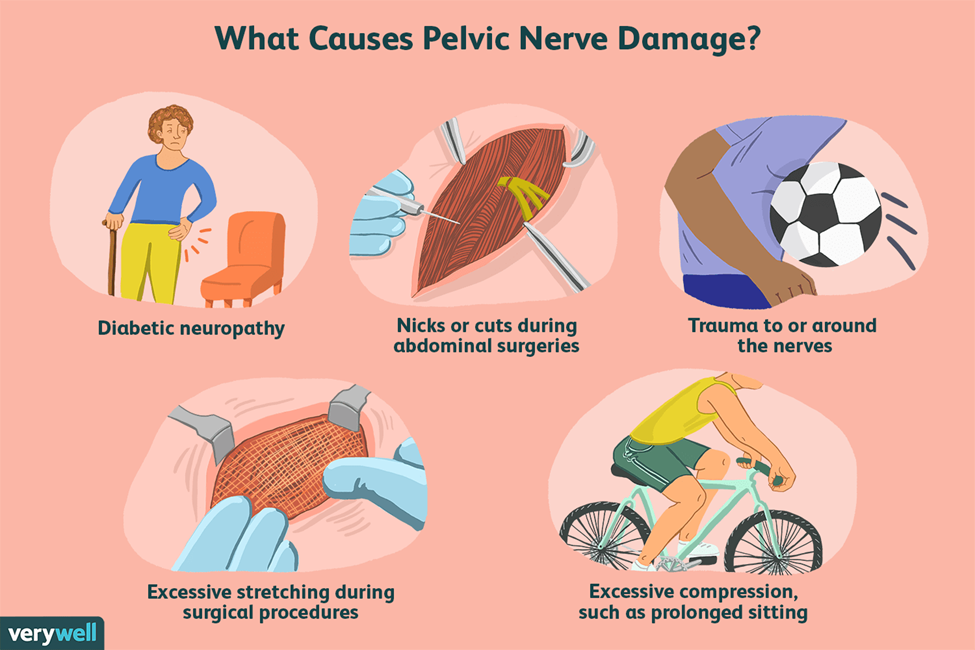

علل میالژی تنش عضلات کف لگنی

علت مستقیم میالژی تنش کف لگن ناشناخته است، اما عوامل متعددی ممکن است در ایجاد آن نقش داشته باشند، از جمله:

آسیب به عضلات کف لگن در حین جراحی یا زایمان

آسیب عصبی

ایستادن یا نشستن بیش از حد طولانی، اسبسواری، روی هم زدن پاها و دوچرخهسواری طولانیمدت نیز میتواند درد لگن مرتبط با این بیماری را تشدید کند.